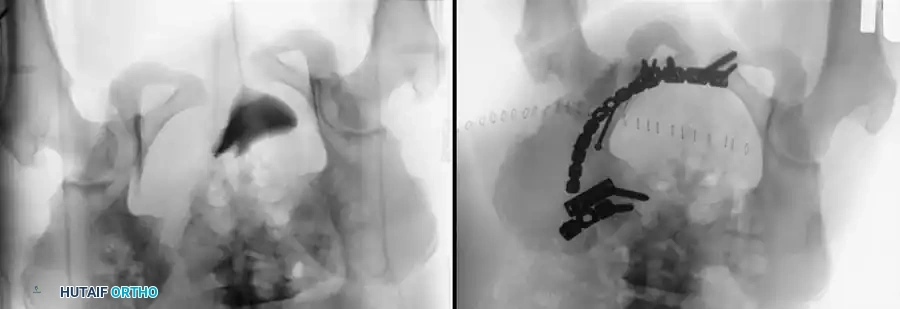

3. Percutaneous Sacroiliac (SI) Screws (Posterior Ring)

The gold standard for posterior ring fixation in appropriately selected patients.

* Indications: Sacral fractures, SI joint disruptions, crescent fractures.

* Technique: Performed under strict fluoroscopic guidance (Inlet, Outlet, and Lateral sacral views).

* Trajectory: The guide wire is advanced from the lateral ilium, across the SI joint, into the S1 (or S2) vertebral body.

* Safety Corridors: The surgeon must possess an intimate understanding of sacral dysmorphism. The "safe zone" is bounded by the sacral neural foramina inferiorly, the spinal canal posteriorly, and the sacral ala anteriorly.

Pitfall: Failure to recognize a dysmorphic sacrum (characterized by upper sacral segment elevation, non-recessed alae, and oblique neural foramina) can lead to catastrophic L5 nerve root injury or vascular penetration during SI screw placement.

Image